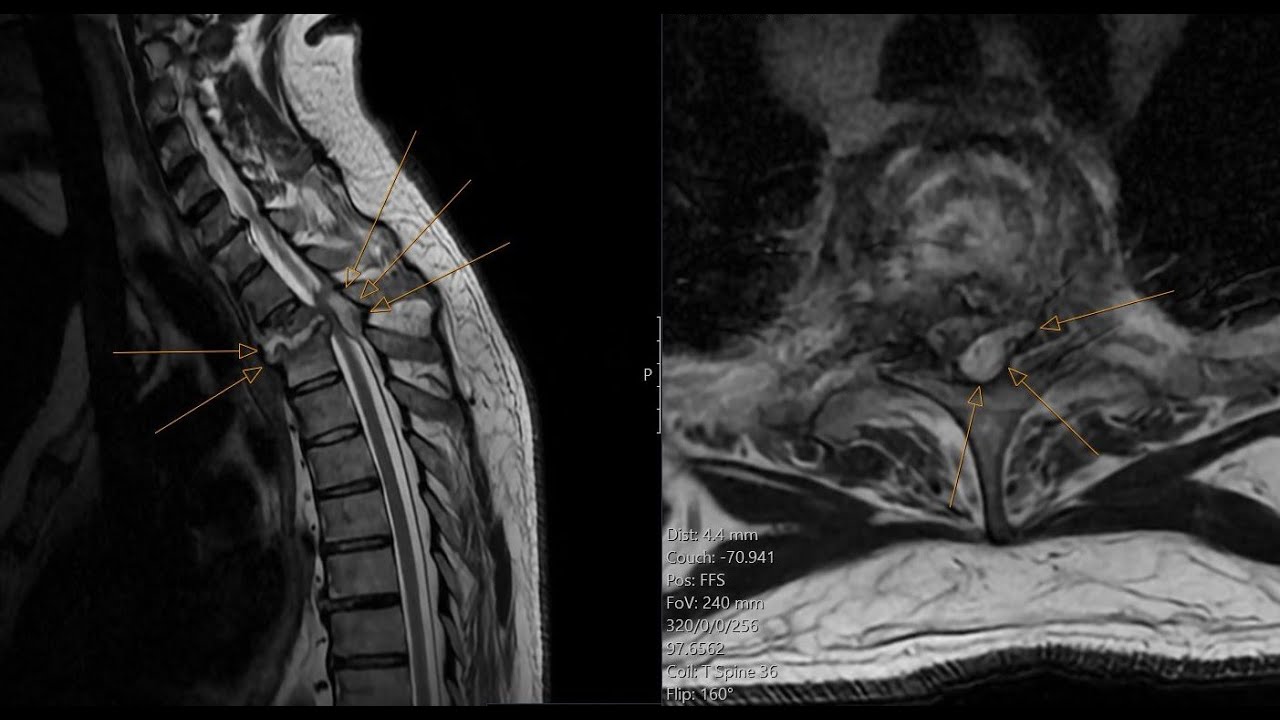

Spinal epidural abscess - spondylodiscitis - insufficiency spinal fracture. CT and MRI correlation.

Описание: Spinal epidural abscess, insufficiency vertebral fracture, spinal canal and foraminal stenosis - complications of spondylodiscitis. Interesting case presentation. CT and MRI correlation.